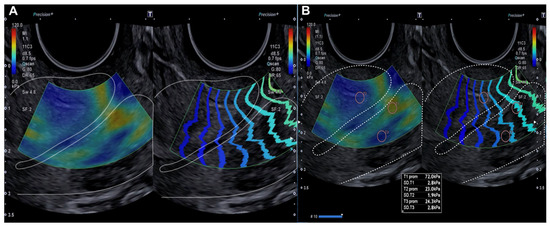

2.2.2. Evaluation Using SonoElastoColposcopy

| Exocervix (kPa) | 19.98 (±9.29) | 105.42 (±36.32) | p < 0.0001 |

| Endocervix (kPa) | 18.5 (±9.07) | 109.8 (±40.86) | p < 0.0001 |